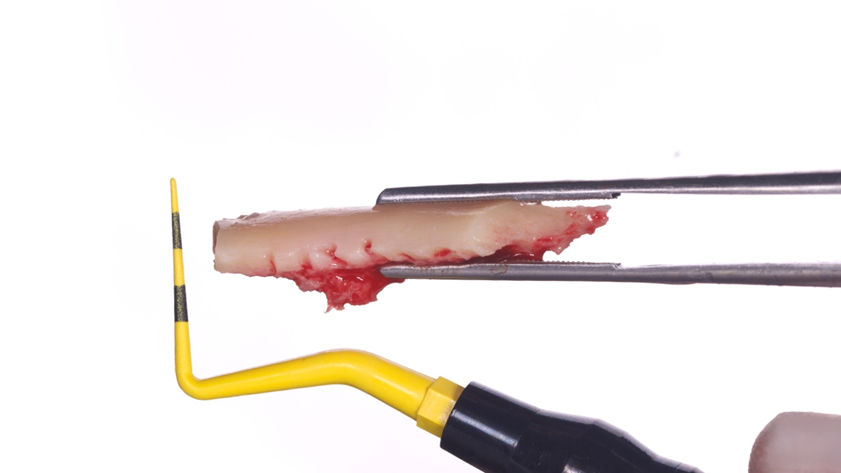

Homem de 60 anos foi encaminhado para reabilitação implantossuportada na região molar inferior direita (Figura 1). O volume ósseo remanescente tridimensional foi acessado por meio de tomografia computadorizada. Revelou uma deficiência vertical de modo que um aumento vertical foi planejado antes da colocação do implante. Seu histórico médico foi verificado e não foram encontradas comorbidades nem condições alérgicas. Não houve achados clínicos intraorais anormais, mas uma deficiência vertical na área molar inferior direita. Nenhum achado anormal foi perceptível no exame extraoral. Um enxerto autógeno em bloco ósseo dividido foi planejado para aumento horizontal e o ramo ipsilateral foi o local doador de escolha. A cirurgia foi realizada sob anestesia local com Articaína 4% e adrenalina 1:100.000. O paciente foi prescrito para enxaguar com Clorexidina 0,12% no pré-operatório, bem como tomar 1mg de Amoxicilina e 8mg de Dexametasona P.O. uma hora antes da cirurgia. Uma incisão mucoperiosteal foi realizada com bisturi número 15C desde o ramo mandibular até a borda mesiovestibular do primeiro pré-molar juntamente com uma incisão perpendicular obliquamente no vestíbulo mandibular. Após o descolamento da mucosa vestibular e liberação do nervo mentoniano, a mucosa lingual também foi descolada (Figura 2). Duas osteotomias verticais e uma horizontal foram realizadas no ramo mandibular com broca 701 para retirada do bloco ósseo necessário à reconstrução horizontal (Figura 3). Após a retirada do enxerto com auxílio de um elevador radicular, o bloco foi cortado longitudinalmente em dois pedaços finos com brocas discais e o osso esponjoso foi raspado para que pudesse ser utilizado como osso lascado (Figuras 4 a 8). Os blocos foram fixados na área edêntula. Um bloco foi fixado na face vestibular e o outro na face lingual. Cada um deles foi fixado com dois parafusos de osteossíntese de 1,5 mm e o osso lascado foi inserido no espaço entre eles (Figuras 9 e 10). A ferida foi fechada com fio de polipropileno 5-0, que foi retirado após 15 dias (Figura 11). A cirurgia cicatrizou sem intercorrências e o paciente recebeu prescrição de amoxicilina 500 mg P.O. a cada oito horas durante sete dias e ibuprofeno 600 mg a cada seis horas durante cinco dias.